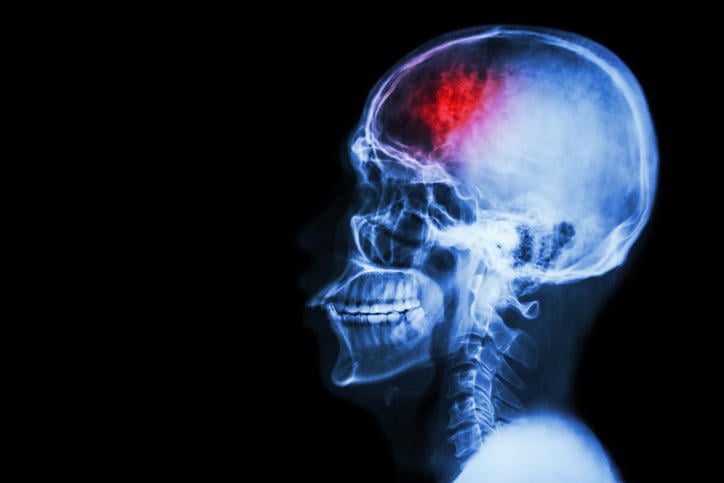

accident vasculaire cérébral (accident vasculaire cérébral) crâne radiologique crâne latéral avec la course et la zone vide à gauche

Un accident vasculaire cérébral se produit lorsque la circulation sanguine est perturbée ou interrompue au niveau du cerveau. Cette perturbation, ou cette interruption, peut être causée par une obstruction (par exemple, la formation d’un caillot sanguin dans une artère cérébrale) ou par une hémorragie. On parle alors d’AVC ischémique ou hémorragique. La rupture d’anévrisme cérébral est une sorte d’AVC hémorragique. Une poche de sang formée sur la paroi d’une artère du cerveau cède soudainement, et le sang se répand dans les zones cérébrales situées à proximité. Pour rappel, les anévrismes peuvent également se former dans l’abdomen, au niveau de l’aorte.